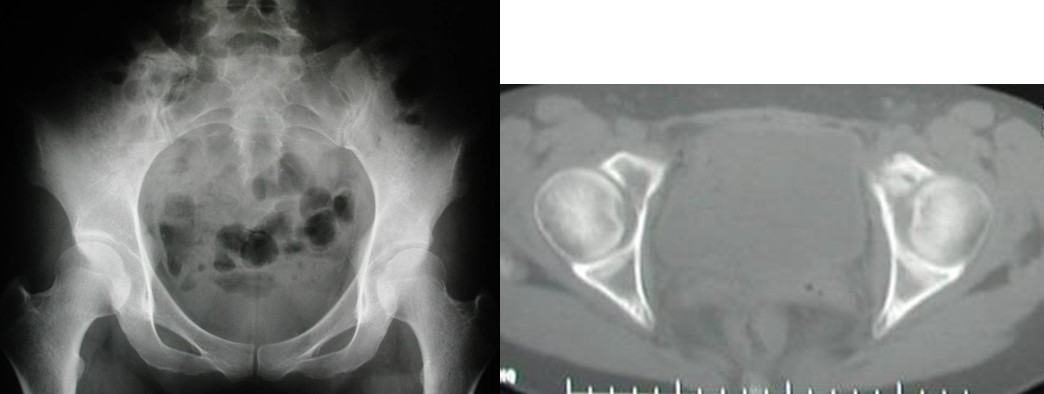

本组病例中不同部位髋臼转移癌的手术方式(图1):I型:髋臼下壁骨破坏、上壁及内、外侧壁完整, 采用肿瘤刮除、普通水泥型全髋置换术。II型:髋臼内、外侧壁破坏,上壁骨质完整, 采用带翼网杯+水泥型全髋置换术。 III型:髋臼上壁及内、外侧壁均破坏,采用肿瘤刮除后、骨水泥填充髋臼上壁骨缺损,带翼网杯+水泥型全髋或组合式人工半骨盆。IV型:孤立性骨盆转移, 以治愈为目的, 采用肿瘤整块切除,组合式人工半盆置换术。

Ⅰ型:髋臼外侧皮质,上方及内侧壁完好,髋臼下及前后方破坏缺损。可以采用骨水泥固定的普通全髋置换术以达到长期牢固固定。手术入路一般采用后外侧入路,不需要大转子截骨,可在髋臼深部放置金属网以加强骨水泥的固定效果,阻挡股骨头向内移位。术后第一天病人即可在耐受范围内下地活动并完全负重。

Ⅱ型:髋臼内侧壁缺损,而周边骨质完好。采用普通髋臼会导致假体及骨水泥早期向内侧移位。对于这种情况,应采用特殊设计的带翼髋臼网杯将应力引至髋臼缘。安装时在保持髋臼假体正确解剖位置的同时需注意将网杯的翼放置在完整的髋臼缘,因为部分髋臼边缘可能存在破坏。可以采用后外侧入路,通常无需大转子截骨,尽量使用长颈人工头,以防止粗隆部撞击网杯延伸缘。股骨粗隆部,股骨干有潜在骨折时,应使用长柄髓内针的人工股骨头。术后第一天病人即可下地负重活动。

图1, 髋臼转移癌的分型示意图(北京大学人民医院)

图2,女,31岁,乳腺癌髋臼转移, Harrington I型

图3,女,55岁,肺癌髋臼转移, Harrington II型